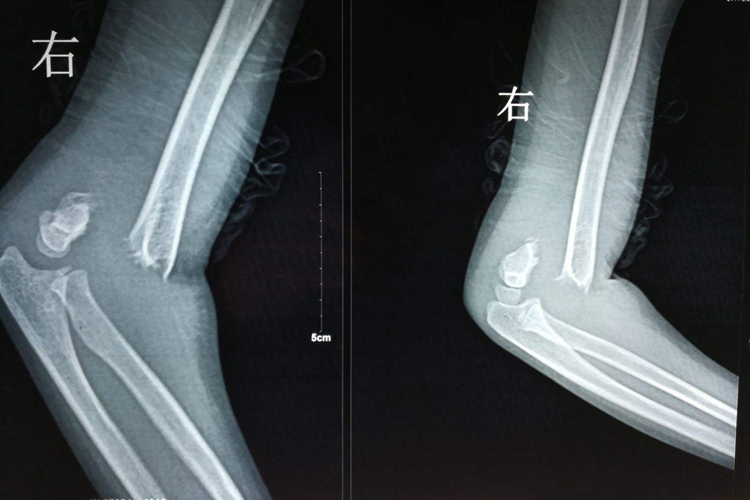

手术治疗:骨折移位明显,桡神经有嵌入骨折断端可能,手法复位可造成神经断裂,应特别小心。手术探查神经时,同时做骨折复位内固定。晚期神经损伤多为压迫或粘连,应考虑手术治疗。